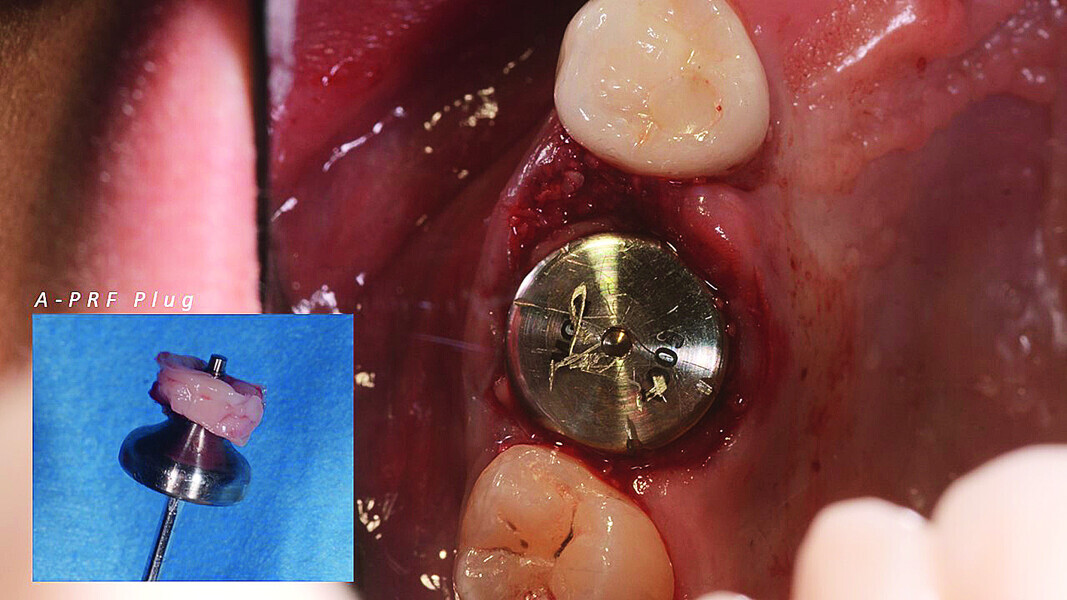

Digital workflow and application of PRF and ozone therapy in oral rehabilitation